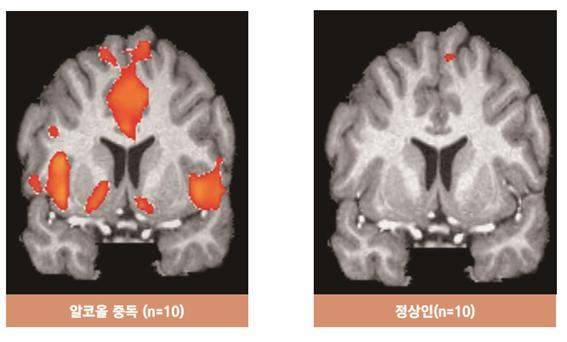

인간의 뇌는 고위중추, 감정중추, 생존중추로 나뉜다. 알코올중독과 관련이 있는 곳은 감정중추다. 감정중추의 주요 부분인 변연계에는 ‘보상회로’가 있다. 보상회로가 자극되면 쾌락과 기쁨 등이 유발되는 도파민이 분비된다. 알코올을 지속적으로 섭취하면 보상회로가 과도하게 자극을 받아 술을 더 많이 자주 마시게 된다. 뇌의 조절능력이 상실된 것이다.

이해국 의정부성모병원 정신건강의학과 교수(중독포럼 상임이사)는 “실제 술과 관련한 사진을 보여줬을 때 정상인의 뇌는 아무런 변화가 없지만 알코올 중독자의 뇌는 쾌락에 작용하는 보상회로가 활성화돼 강하게 반응했다”고 말했다. 이 교수는 “알코올 중독자들은 ‘마지막으로 딱 한번만 더!’를 수 없이 외치지만 중독이 진행됨에 따라 억제능력이 계속 저하돼 알코올에 의존할 수밖에 없다”고 덧붙였다.